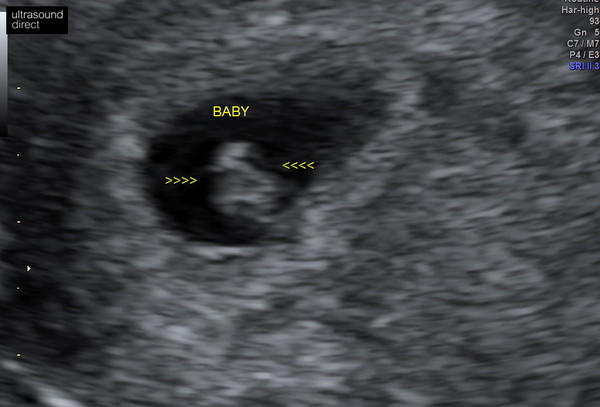

Scan went so well... I broke down as soon as I laid on the table as I was so scared but she found baby so fast and the heart beat was pounding away. I'm 6+5 today and baby was measuring 7.7mm yesterday. So reassuring as I've had horrendous cramping. Put a pic up too :)

So pleased @BlueberryPoppy123 it’s so lovely to see isn’t it and a great relief. I’m already counting down the days to my next scan! X

@sunshine8888 it is. Probably have about 6 weeks until my next scan :( I just hate at the beginning when you don't have that reassurance of listening to heart beat on a Doppler and you can't feel kicks and there's no certainty everything is ok...

@BlueberryPoppy123 that's so exciting little baba 😁😁😍

Lovely scan @BlueberryPoppy123 so it went well!